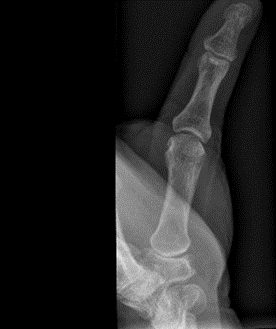

X-ray showing subluxation, joint space narrowing, sclerosis and osteophytes, with a Robert’s view on the right

An X-ray can be used to confirm the diagnosis. Views of the base of the thumb, including a PA, lateral, and Robert’s view (hyper-pronated) should be done. This will show subluxation of the carpometacarpal joints (CMCJs), with joint space narrowing, sclerosis, osteophytes and cysts.